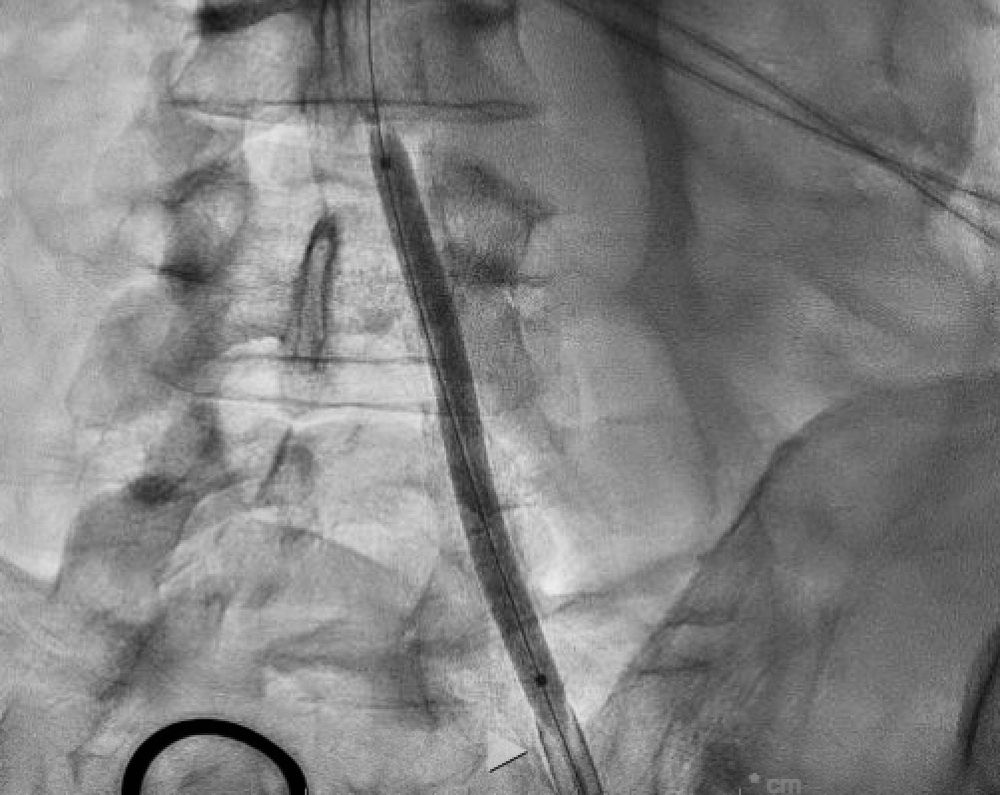

1/2 Ostial-thru-mid RCA calcified πŸͺ¨CTO: referred to our Team after prior failed attempts. Started Retro surfing πŸ„β€β™‚οΈ but no suitable Septals (primarily telephone πŸ“ž cord epicardial collaterals). Pivoted to AWE. Got subintimal purchase with P200πŸ‘β€¦

2/2 Then true-lumen from Ostium into RV Marginal with Mongo wire. Then 2nd Mongo wire true lumen to RPLB via Sasuke dual-lumen microcatheter. All 3 wires visible below. Final switch to Marvel workhorse wire for IVUS πŸ‘οΈ guided PCI/DES (ostium to crux)πŸ‘β€¦